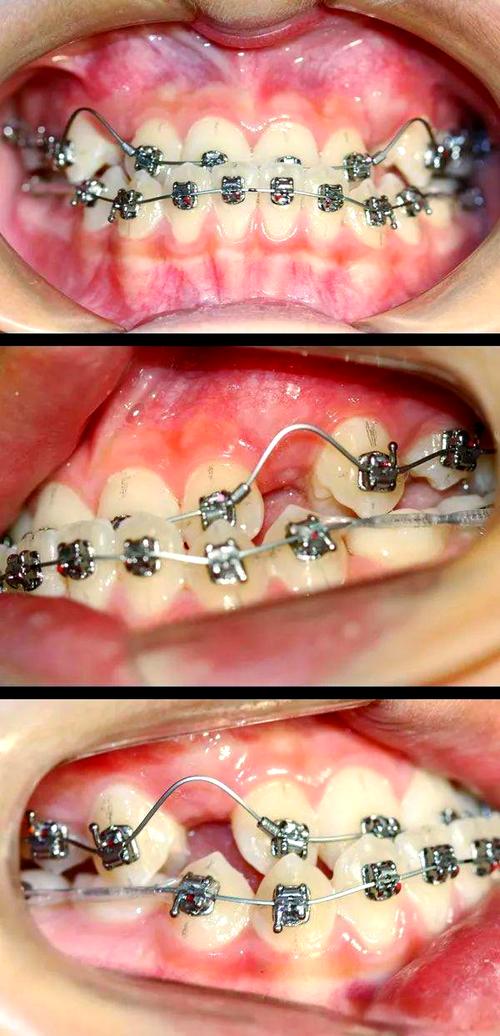

- 技术与方案:根据病情选择合适技术,如儿童早期反颌可能需要功能性矫治器(如FR-III、 twin-block),成人骨性反颌可能需正畸-正颌联合治疗,隐形矫正则适合对美观要求高的患者。